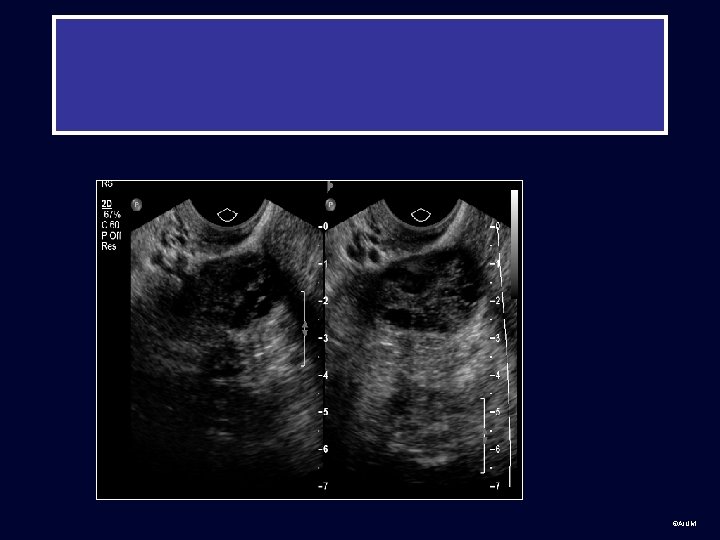

Technique • Transabdominal sonography uses a distended bladder as window to pelvic structures for a global view. ©AIUM

Transabdominal Sonography Bladder Vagina Uterus CX Ovaries • Sagittal and transverse views of the pelvis • Uterus on sagittal has “teardrop” appearance ©AIUM